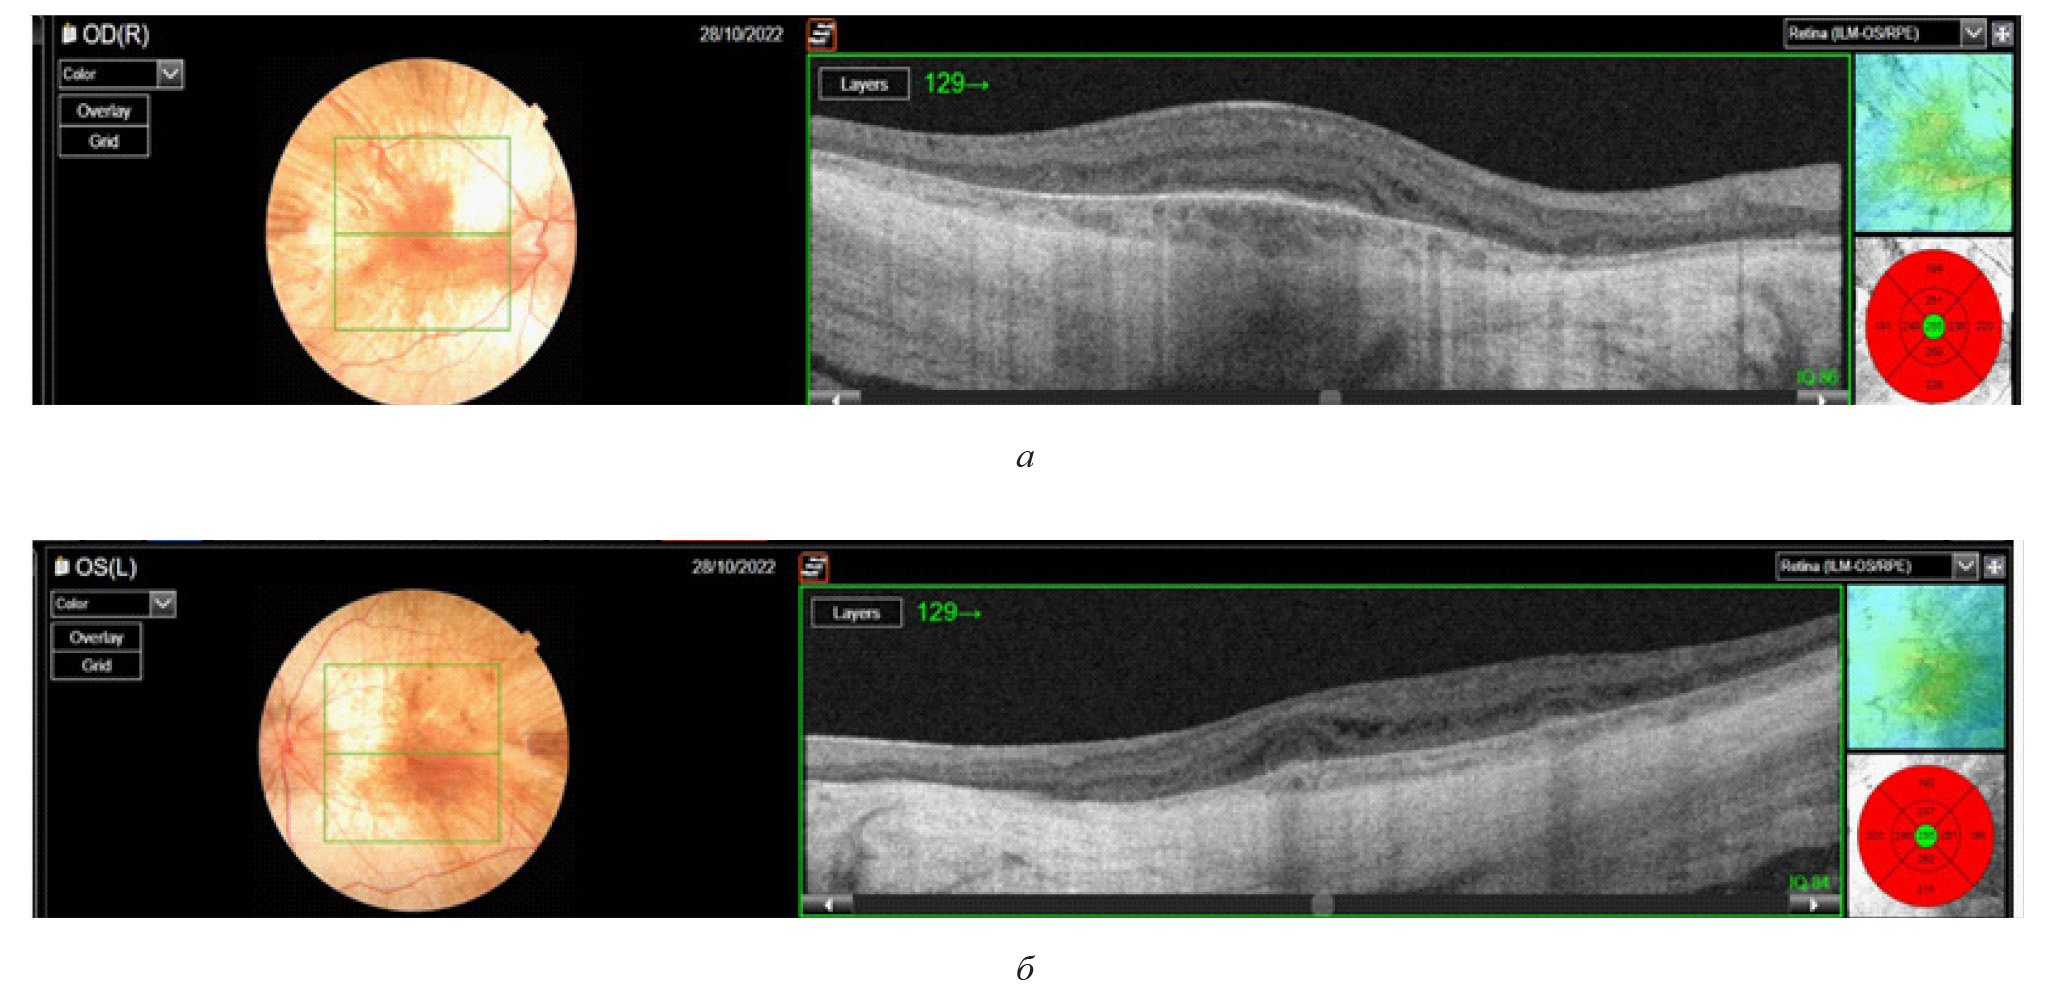

Были проведены следующие исследования: фоторегистрация глазного дна с помощью фундус-камеры оптического когерентного томографа Mirante (рис. 3 а, б), исследование аутофлюоресценции глазного дна (рис. 3 в, г), ОКТ макулярной зоны (прибор DRI OCT Triton) (рис. 4 а, б). По данным ОКТ определялось отсутствие линии сочленения наружных и внутренних сегментов фоторецепторов в фовеа, что является важным структурным маркером дегенеративных изменений сетчатки, при этом наблюдалась сохранность фоторецепторов в зоне фовеа. Эти результаты согласовались с клинической картиной хороидеремии и свидетельствовали о выраженных дегенеративных изменениях в сетчатке и сосудистой оболочке глаза. Сохранность фоторецепторов в зоне фовеа объясняла относительно высокое сохранение центрального зрения, несмотря на общую дегенерацию сетчатки. Пациенту была выполнена электроретинография ERG OU стандарт (Tomey EP-1000): амплитуда и латентность «а» волны была снижена при максимальном и колбочковом ответе, что свидетельствовало о нарушении функции фоторецепторов в центре и на периферии.

Рис. 4. Оптическая когерентная томограмма (прибор DRI OCT Triton) макулярной области сетчатки пациента Х.: а, б – нарушение трехслойной структуры наружных слоев сетчатки на всем протяжении скана, включая субфовеальную зону, кистозный макулярный отек в средних и внутренних слоях сетчатки, полное истончение сосудистой оболочки, вследствие чего визуализируется прилежащая склера